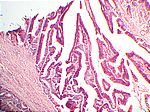

Adenocarcinom des Dickdarms, HE